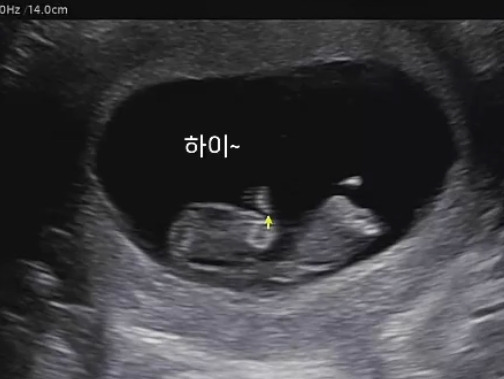

오랜만에 초음파를 보러 간 날. 10주 차이다. 이제는 누워서 배초음파로 편하게 볼 수 있었다!

초음파 기계를 대자마자 어느새 커져버려 마치 햄스터처럼 생긴 아기가 보였다. 손도 위아래로 움직이더니 다리까지 힘차게 움직이며 발차기를 하는 모습도 보였다! 나는 아무것도 느낄 수 없었지만 내 몸속에서 이렇게 열심히 움직이고 있다니 보고도 믿기지 않았다. 초음파 화질이 좋아서 정말 작은 손가락 발가락 모양도 볼 수 있었고 심장이 잘 뛰고 있는 것도 확인할 수 있었다. 이렇게 처음으로 움직이는 아기를 마주하게 되었다!

어플을 통해서 저장된 동영상을 다운로드하여 몇 번을 보았다. 손을 움직이고 발을 차는 모습, 그리고 발가락 모양이 잡힌 것을 몇 번이나 돌려보았다. 몸은 힘들지만 마음은 가벼웠다.